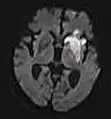

DWI showing restricted diffusion in the medial dorsal thalami consistent with Wernicke encephalopathy

DWI showing cortical ribbon-like high signal consistent with diffusion restriction in a patient with known MELAS syndrome